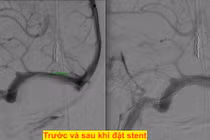

Bệnh lý hẹp xoang tĩnh mạch nội sọ ít được biết đến, việc hẹp này gây nên hai hậu quả là tăng tốc độ dòng chảy qua chỗ hẹp và ứ trệ tuần hoàn tĩnh mạch trong não. Bệnh gây đau đầu, ù tai, nhìn mờ và đột quỵ...